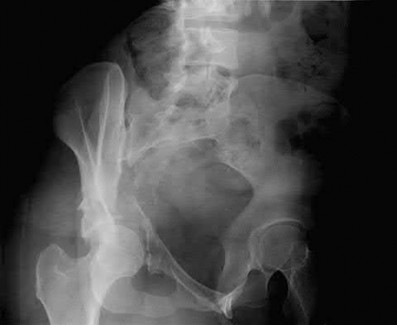

Which of the following images shows an injury pattern most consistent with a lateral compression type 3 pelvic ring injury?

Figure C is an axial CT scan of a lateral compression type 3 (LC3) pelvic ring injury.

Classically, LC3 injuries demonstrate an ipsilateral lateral compression and a contralateral APC (windswept pelvis) fracture pattern. The most common mechanism of injury in these cases is a rollover MVC or pedestrian vs. auto. LC1 injuries are characterized by an oblique or transverse ramus fracture and ipsilateral anterior sacral ala compression fracture, while LC2 injuries consist of a rami fracture and ipsilateral posterior ilium fracture dislocation (crescent fracture). While LC1 injuries can often initially be managed conservatively with protected weight-bearing and close observation, LC2 and LC3 pelvic ring injuries are almost universally operative.

Answer 1: This represents a lateral compression type 2 injury. Answer 2: This represents a lateral compression type 1 injury.

Answer 4: This represents an anterior posterior compression type 2 injury. Answer 5: This represents an anterior posterior compression type 3 injury.